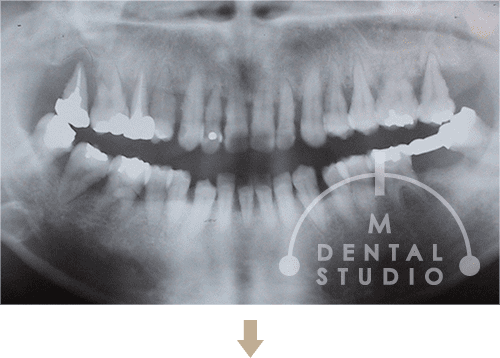

治療開始前は、親知らず合わせ29本の歯が存在していましたが、そのの8割以上が動揺し、激しい腫れと激しい口臭と頻発する口内炎が口の中の状態でした。上下の歯が噛み合うだけで「ビアノの鍵盤のように」が動くのが、この患者様の口の印象でした。

前の数本が、いつ抜けるのか分からないため、余っていた矯正用のブラケットで仮固定をして、写真を撮りました。歯石が多く付着しているため歯周検査もままならずですので、仕方ない手段でした。治療期間1年4ヶ月でしたが、着実に結果につながり、抜は親知らず合わせ6本(親知らず3本)、たったインプラント2本で終了できた事は、大きな成果と治療プロセスが明確であった事と思います。